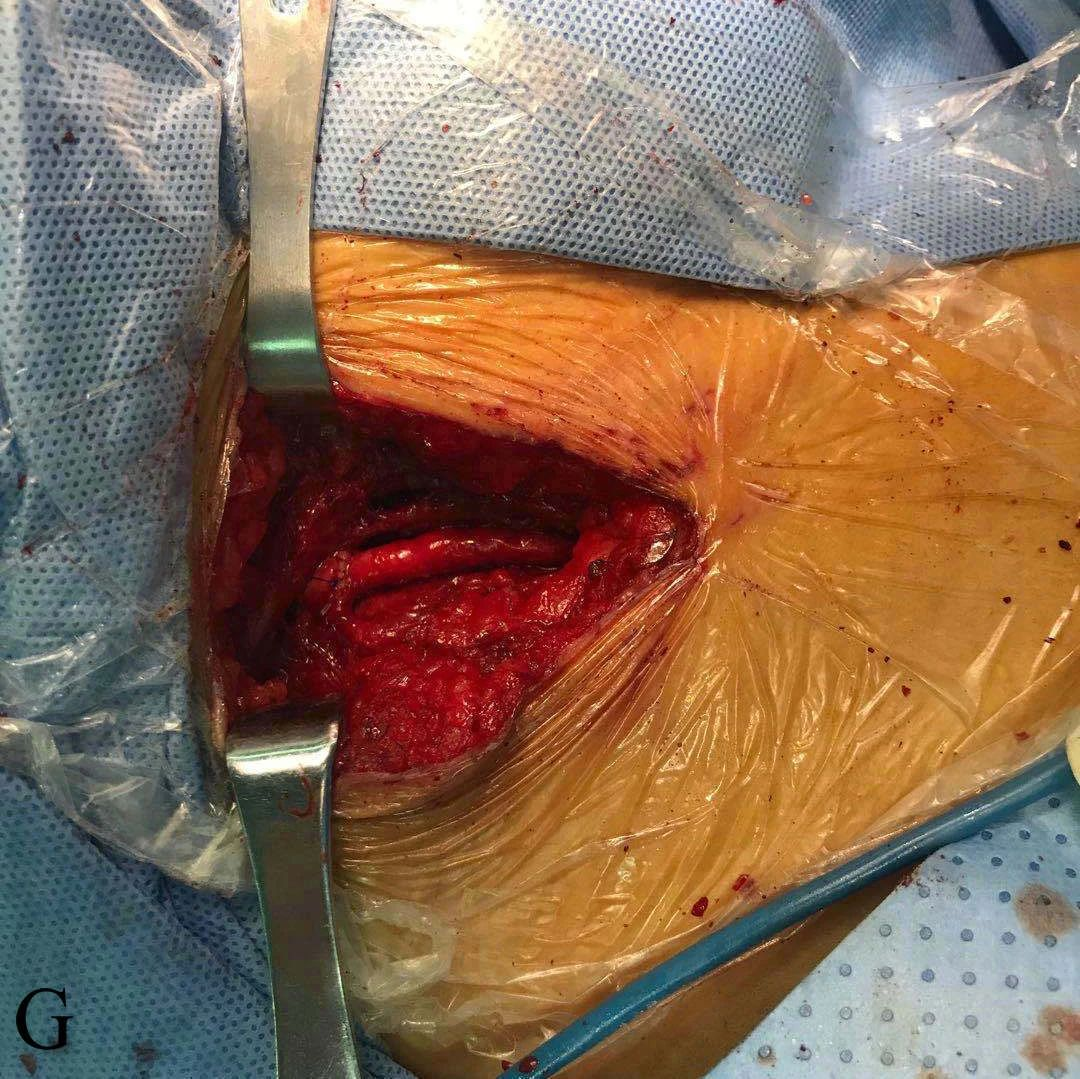

G:股动脉切开取栓